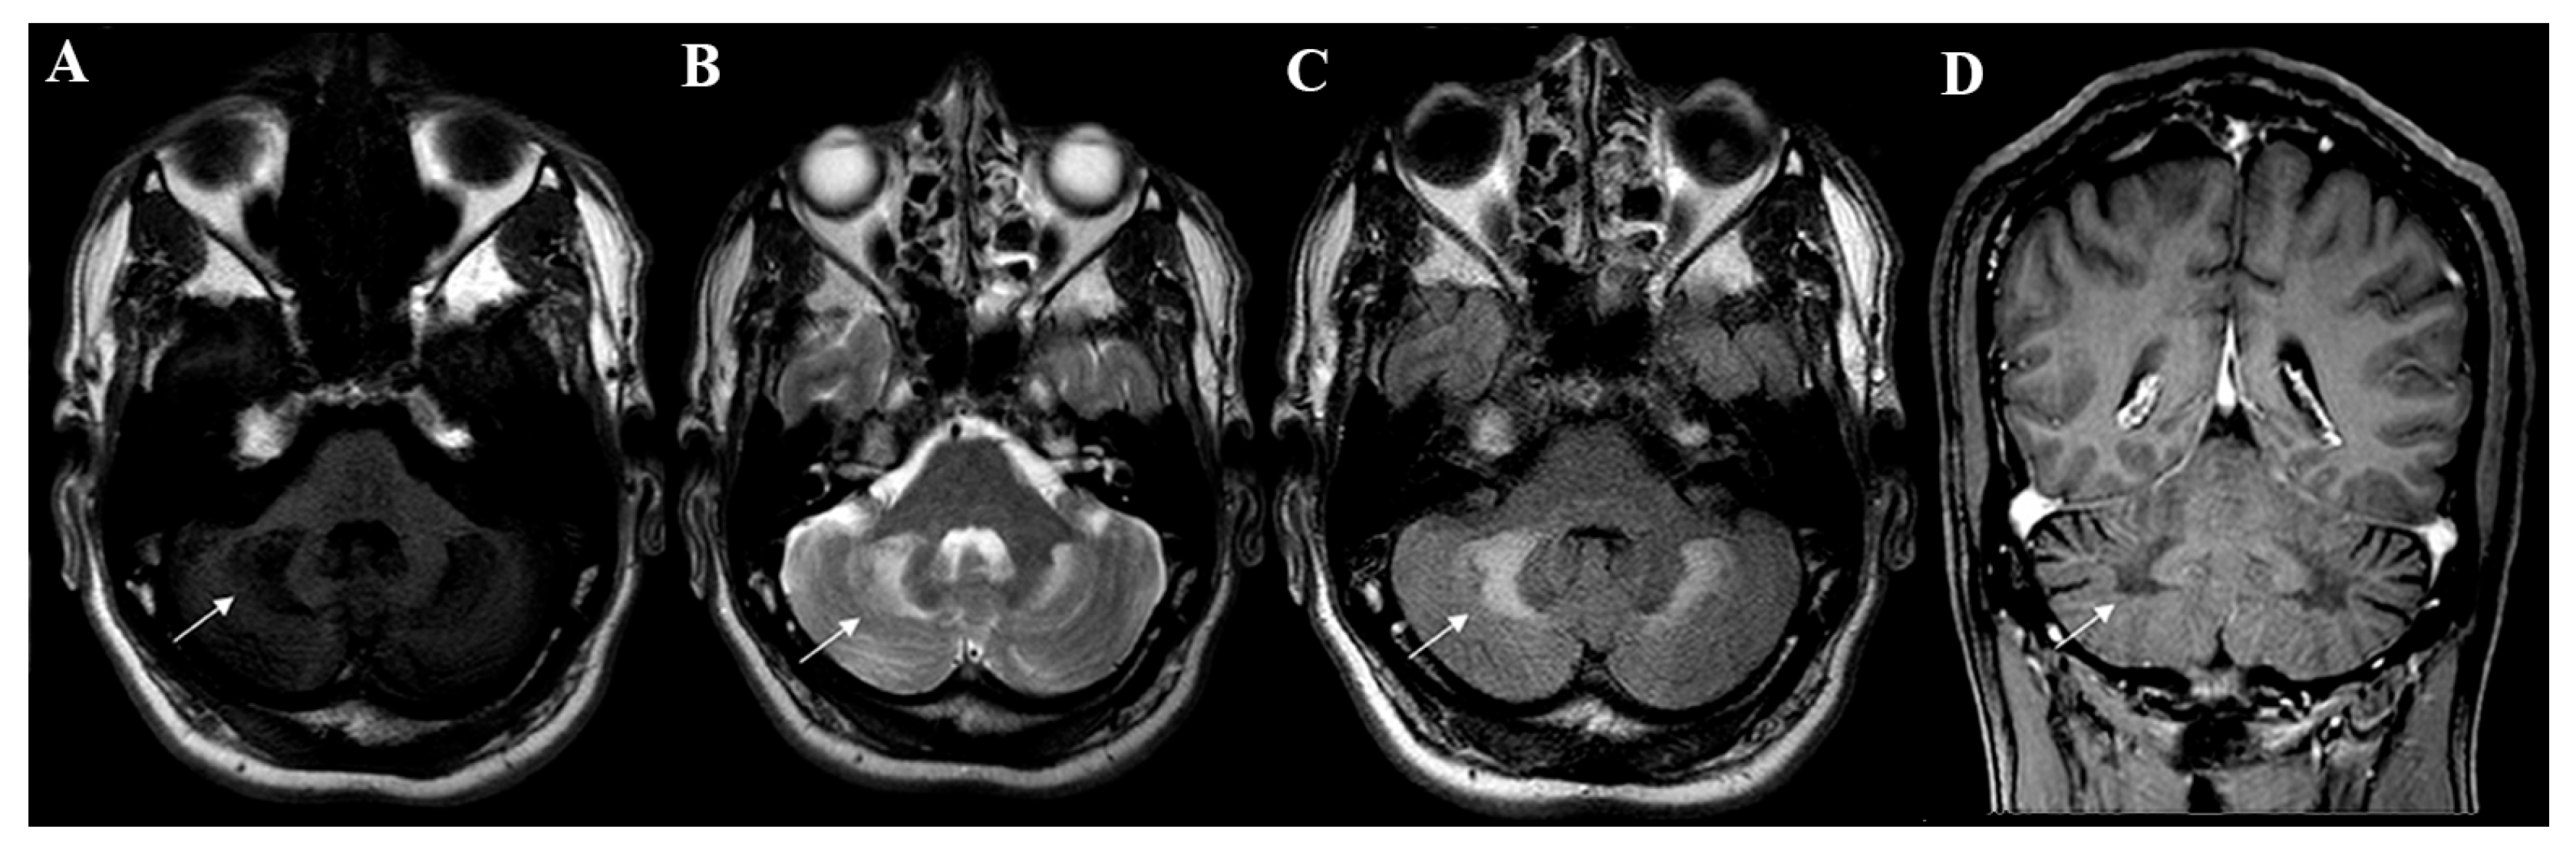

Inoue et al. (1999) [37] conducted an experiment with rats on a hypercholestanolemic diet and concluded that cholestanol induces apoptosis of the cerebellar neuronal cells, especially for Purkinje cells, a factor that led the rats to present ataxia and tremor. Bogaert et al. (1969) [38]. described the autopsy of ataxic CTX patients, demonstrating the destruction of the dentate and fastigial nucleus, in addition to a reduction in Purkinje cells. Those histologic alterations were manifested in magnetic resonance neuroimaging studies as signal intensity changes in the deep cerebellar white matter and particularly in the dentate nucleus (Figure 2).

Figure 2.

Neuroimaging patterns observed in CTX. Axial brain MRI disclosed signal change in deep cerebellar white matter and dentate nucleus (white arrows) which were hypointense on T1W (A) and hyperintense in T2W (B) and FLAIR sequences (C). Coronal brain MRI showed hypointensity in the deep cerebellar white matter on T1W imaging (D).